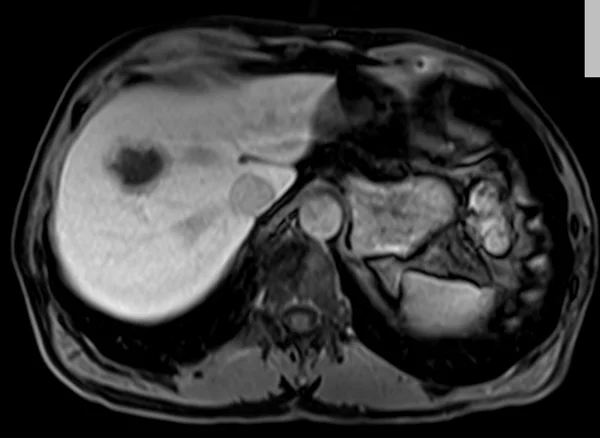

delay 5min 1 - MRI